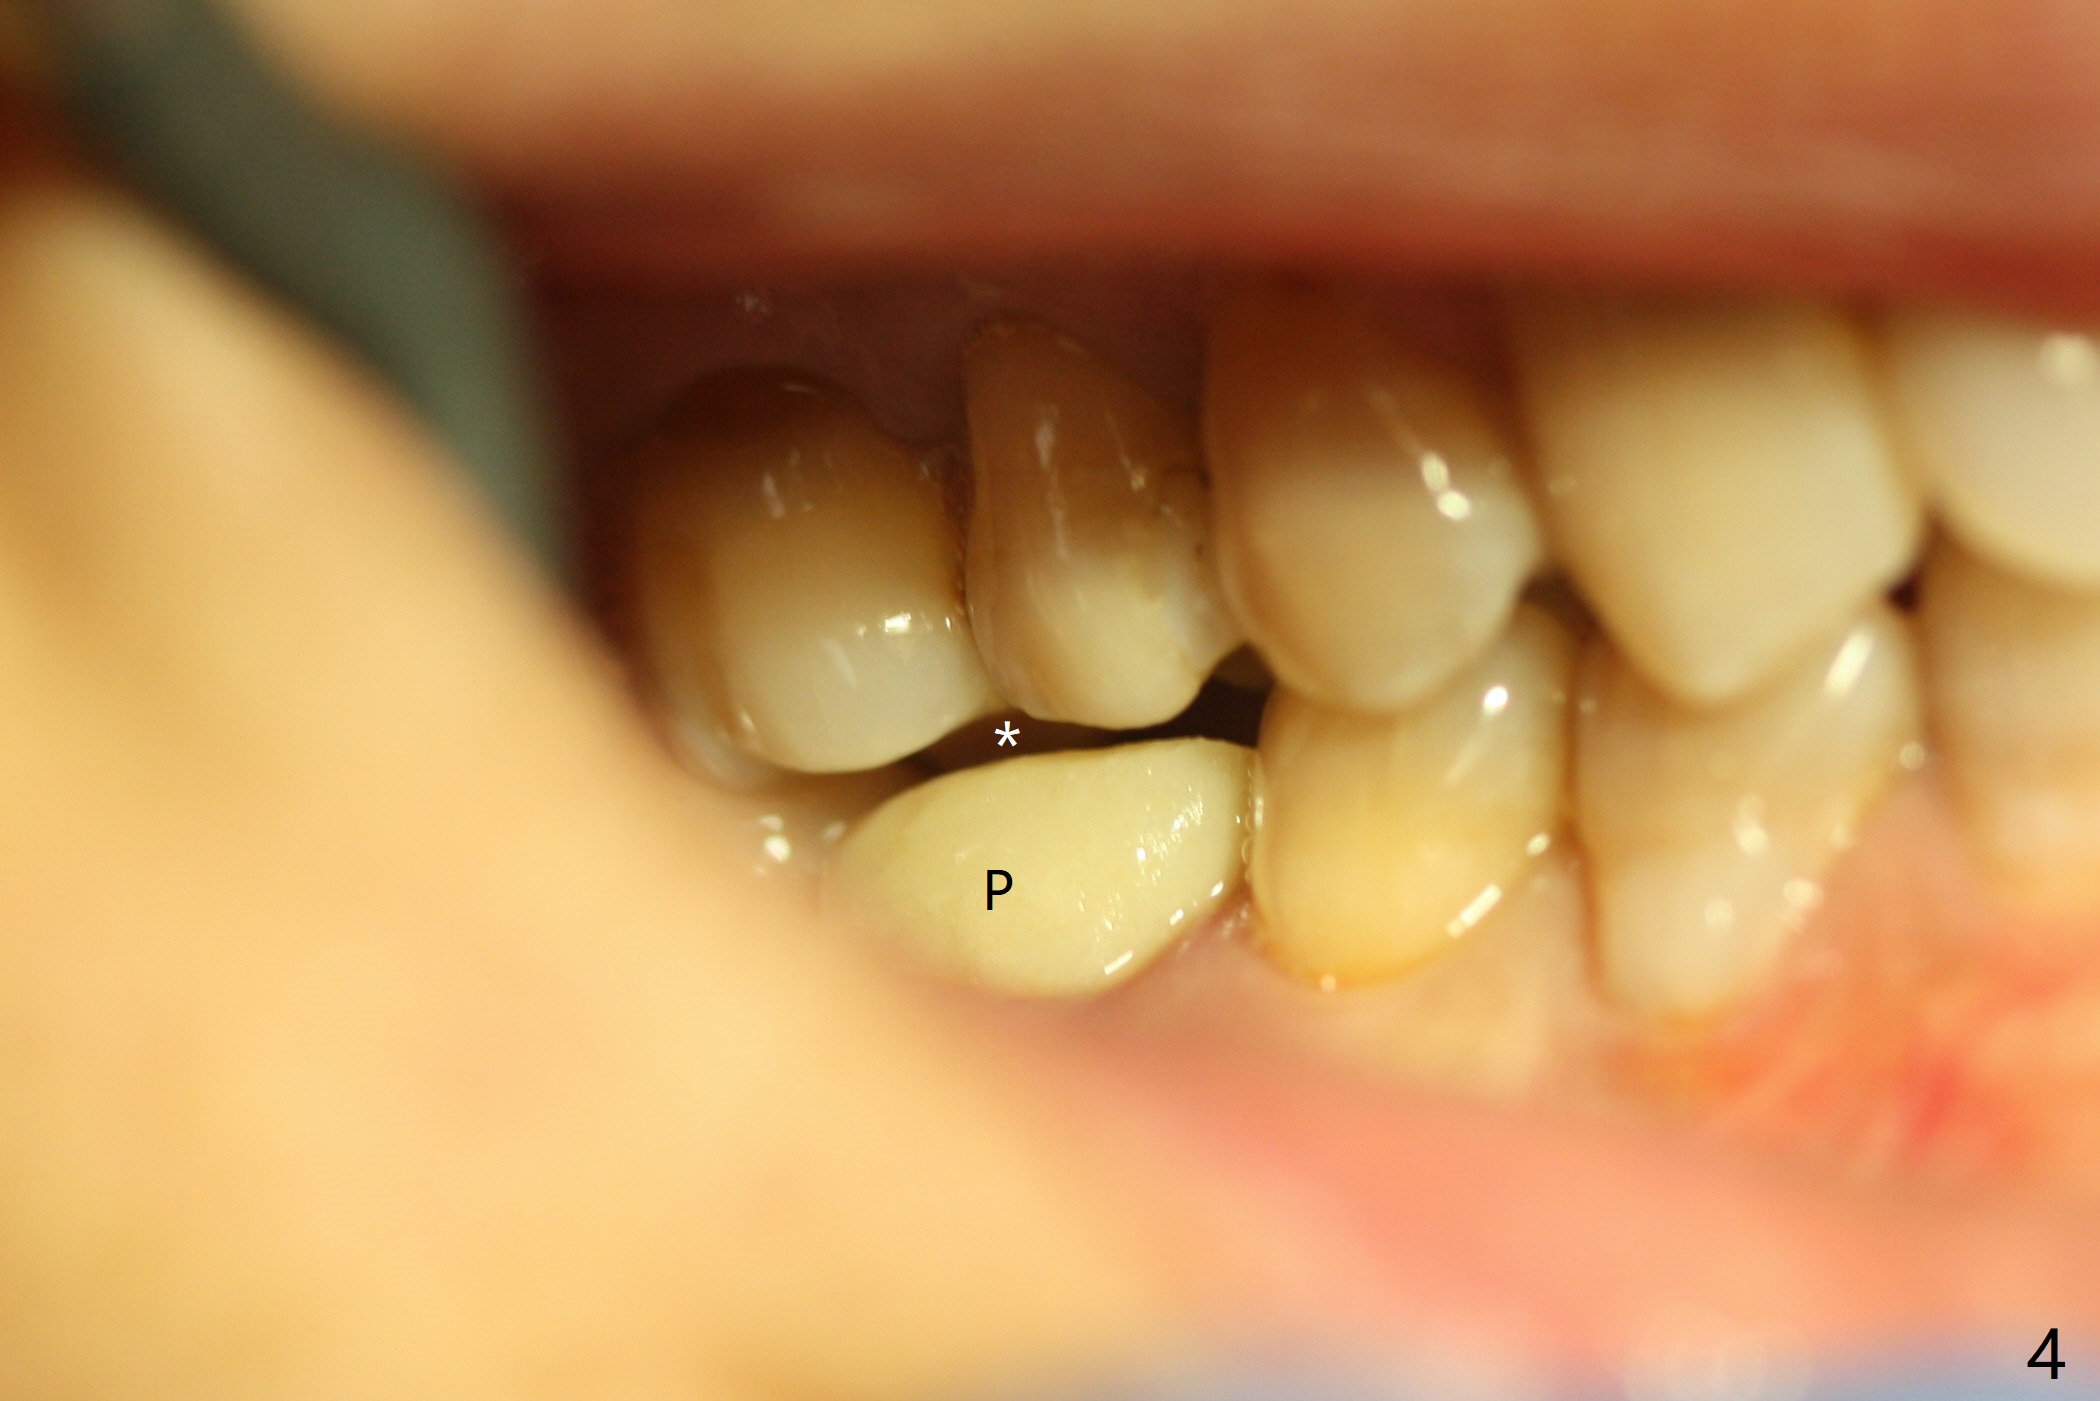

After extraction of #30 (Fig.1 (S: septum)), a 5x11.5 mm implant is placed with guide mainly in the mesial socket (mesial to the septum (S) with >35 Ncm; after immediate placement of a 6.5x4(3) mm abutment, allograft is placed (Fig.2 *). An immediate provisional is fabricated to hold the bone graft in place (Fig.3 P). To prevent micro-movement, the provisional has clearance from the opposing dentition (Fig.4 *, nonfunctional). There is not too much loss of bone graft 4 months postop (Fig.5). In fact the mesial and distal sockets heal. The implant plateau is covered with the bone 8 months post cementation (Fig.6 arrowheads ( *: addition of porcelain for the distal gingival embrasure)).